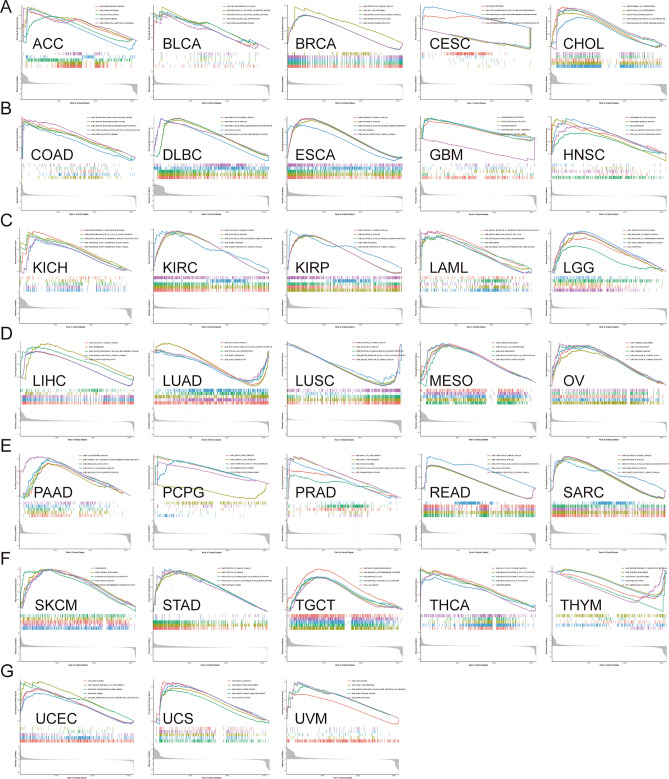

Functional analysis of HS6ST2

To ascertain the biological character of HS6ST2 in a range of tumor tissues, GSEA was performed. The resulting GO function is shown in Fig. 12. The data revealed a positive correlation of HS6ST2 with the detection of chemical stimuli in breast invasive carcinoma, lymphoid neoplasm diffuse large b-cell lymphoma, esophageal carcinoma, kidney renal clear cell carcinoma, liver hepatocellular carcinoma, sarcoma, stomach adenocarcinoma, kidney renal papillary cell carcinoma, and rectum adenocarcinoma, but the correlation was negative in lung squamous cell carcinoma. Similarly, GO BP analysis revealed a favorably correlation between HS6ST2 expression and ncRNA processing in adrenocortical carcinoma, kidney renal clear cell carcinoma, kidney renal papillary cell carcinoma, prostate adenocarcinoma, cervical squamous cell carcinoma and endocervical adenocarcinoma, and rectum adenocarcinoma. As seen in Fig. 12B,G, HS6ST2 correlated favorably with the degree to which genes were silenced in uterine corpus endometrial carcinoma, uveal melanoma, lymphoid neoplasm diffuse large b-cell lymphoma, and esophageal carcinoma. In contrast, HS6ST2 was negatively correlated with epithelial cell differentiation in lung adenocarcinoma, but the correlation was positive in cholangiocarcinoma and mesothelioma.

The top five KEGG pathways significantly connected with HS6ST2 expression in each tumor are shown in Fig. 13. Positive correlations were found between HS6ST2 expression and the cytosolic DNA sensing pathway and antigen processing and presentation in prostate adenocarcinoma, skin cutaneous melanoma, and stomach adenocarcinoma, but the correlations were negative in pancreatic adenocarcinoma. In contrast, in rectum adenocarcinoma and brain lower grade glioma, HS6ST2 expression was inversely correlated with the porphyrin and chlorophyll metabolism pathways and the metabolism of xenobiotics by cytochrome P450, while the correlation was positive in head and neck squamous cell carcinoma. As shown in Fig. 13A,B, the Toll-like receptor signaling pathway was negatively correlated with HS6ST2 expression in bladder urothelial carcinoma and pancreatic adenocarcinoma. In addition, HS6ST2 was favorably connected with steroid hormone biosynthesis and drug metabolism in breast invasive carcinoma, while the correlation was negative in lung adenocarcinoma and brain lower grade glioma.

Despite the emergence of newer technologies and tailored therapeutics, resistance to drugs remains a major problem for researchers in the laboratory and clinic, and new drug resistance-combating strategies have been developed, such as restoring the function of tumor suppressor genes42 and RNA interference43. We determined the correlation of HS6ST2 with the IC50 values of over 750 anti-cancer medications. The data showed that increased HS6ST2 expression was correlated with reduced sensitivity to numerous drugs, indicating its probable participation in medication resistance; in contrast, increase HS6ST2 expression was correlated with increased sensitivity to afatinib, BMS754807, gefitinib, and TAE684. This discovery suggests that modulating the expression of HS6ST2 may be a strategy for enhancing anticancer drug efficacy. Finally, our enrichment studies implied that HS6ST2 may influence the pathophysiology and/or etiology of cancer by functioning in RNA processing, gene silencing, epithelial cell differentiation, the cytosolic DNA sensing pathway, antigen processing and presentation, and/or drug metabolism. According to these results, HS6ST2 may regulate tumor development via these mechanisms. In addition, a number of experiments were conducted to evaluate the expression of HS6ST2 in LUAD tissues. HS6ST2 was increased in LUAD tissues compared to nearby normal tissues.